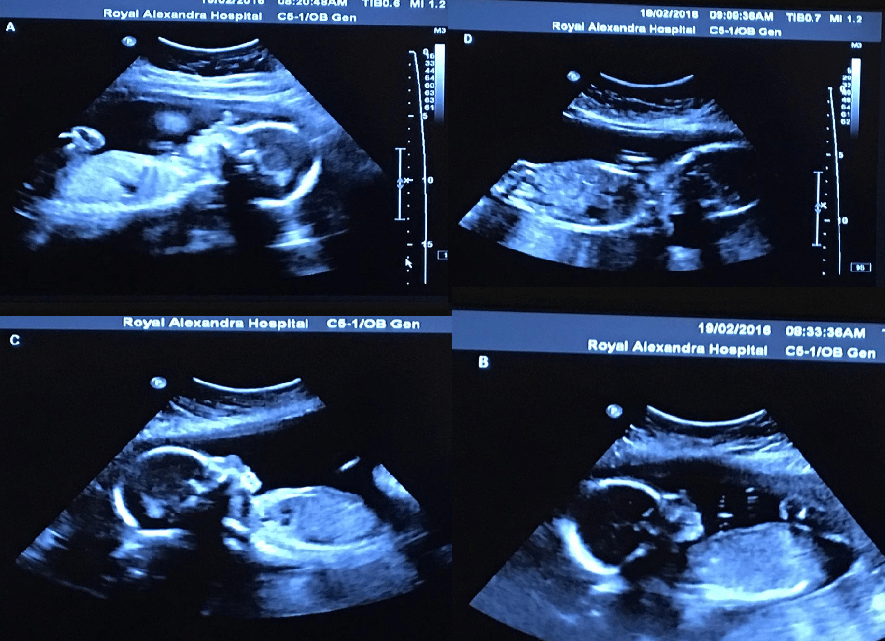

Three months after Bethani became pregnant she went in for an ultrasound that revealed she wasn’t just expecting one baby, but the young woman was pregnant with quadruplets! And, these weren’t just any quadruplets, they were identical. This occurance is so rare that nurses estimated the chances of Bethani conceiving quadruplets naturally to be only one in fifteen million! Everyone was shocked to learn this news, but the couple was still ecstatic and eager to welcome these 4 baby girls into their lives!

“It was completely and totally natural. It was very spontaneous,” Bethani said. “She turned the screen and she started counting babies and she counted baby one, baby two, baby three and baby four. I’m definitely glad I was laying down because I could not believe that there were four there. I thought there had to be some kind of mistake… (my husband) almost fainted. He had to sit down for a moment.”